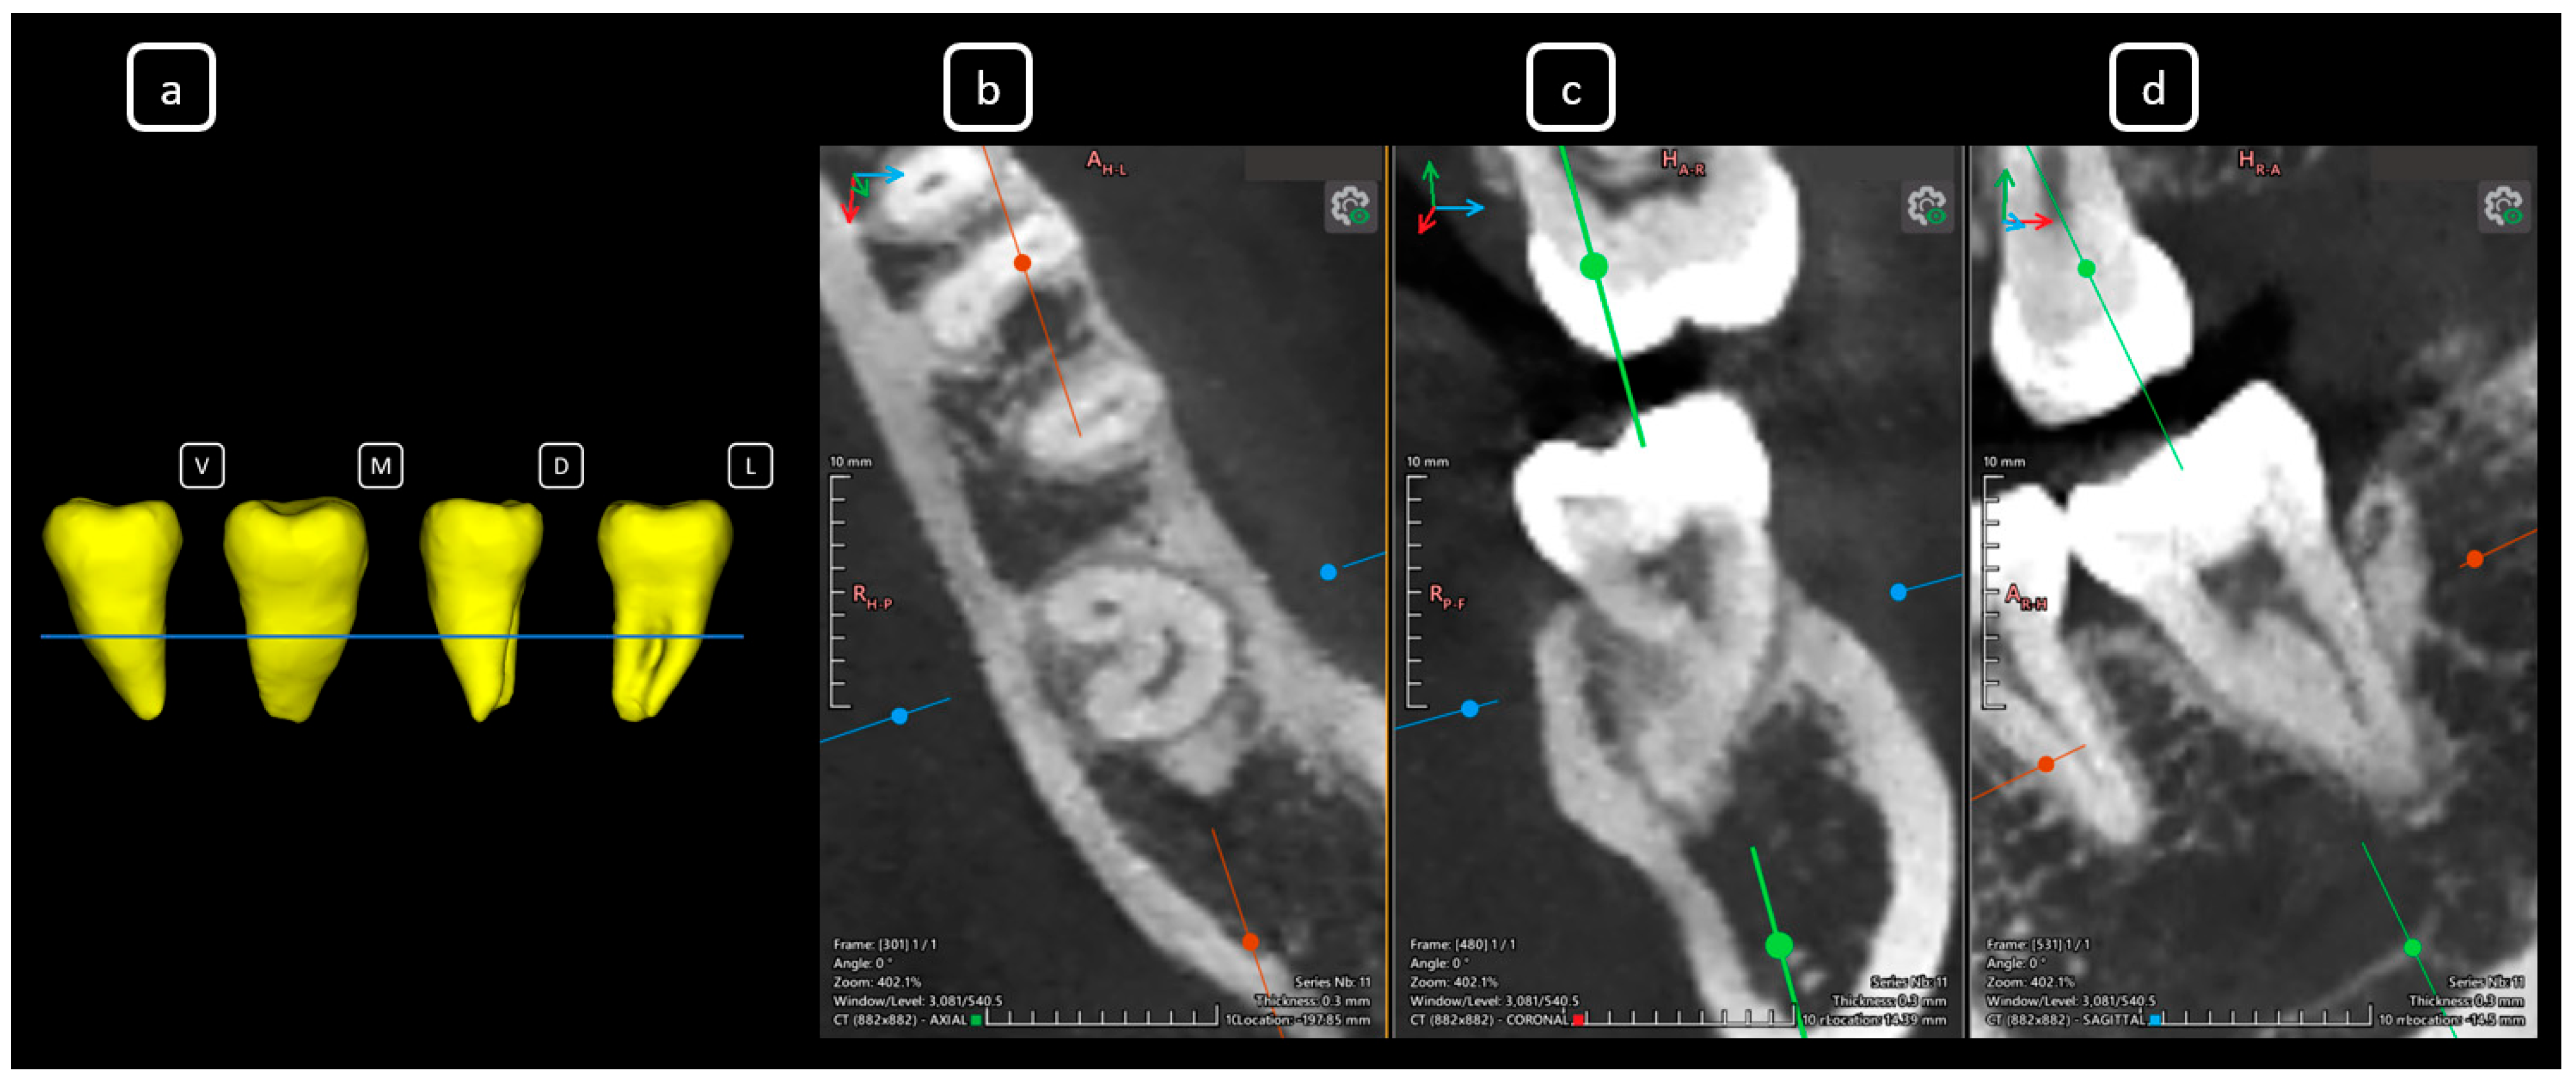

Imaging Findings of Clinical Significance in Endodontics During Cone Beam Computed Tomography Scanning of the Upper Airway—The Anterior, Bilateral, C-Shaped, Dual of Mandibular Root Canals: A Brief Case Report

García-Torres, E.; Guerrero-Falcón, D.L.G.; Bojórquez-Armenta, H.A.; Almeda-Ojeda, O.E.; Barajas-Pérez, V.H.; Solís-Martínez, L.J. Imaging Findings of Clinical Significance in Endodontics During Cone Beam Computed Tomography Scanning of the Upper Airway—The Anterior, Bilateral, C-Shaped, Dual of Mandibular Root Canals: A Brief Case Report. Diagnostics 2025, 15, 3157. https://doi.org/10.3390/diagnostics15243157